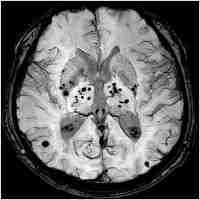

| Abstract | INTRODUCTION The new MRI techniques introduced in the last decade allowed the detection of cerebral microbleeds (CMBs) in different groups of diseases: stroke, Alzheimer disease, vascular dementia or healthy people of advanced age. CMBs are radiologically defined as small, rounded, homogeneous, hypointense lesions on T2*-weighed gradient-recalled echo (T2*-GRE) sequences. OBJECTIVE AND METHOD We evaluated the prevalence, number and location of CBMs in a cohort of 26 consecutive cerebral hemorrhage patients admitted in the National Institute of Neurology and Neurovascular Diseases. We also assessed the association between CMB, classical vascular risk factors and small vessel disease. RESULTS AND CONCLUSIONS From the 26 patients, 2 patients had secondary intracerebral hemorrhage (ICH) (hemorrhage in metastasis, respectively a cavernoma). From the 24 ICH patients 12 have had at least 1 CMB lesion. The average volume of the cerebral hemorrhage was larger in patients with CMBs, with a relative increase of 42%. Small vessel disease was associated with a significant increase in the presence of CMBs (relative increase of 86%). In both cases, however, since the number of patients enrolled was small, the correlations did not reach statistical significance. |